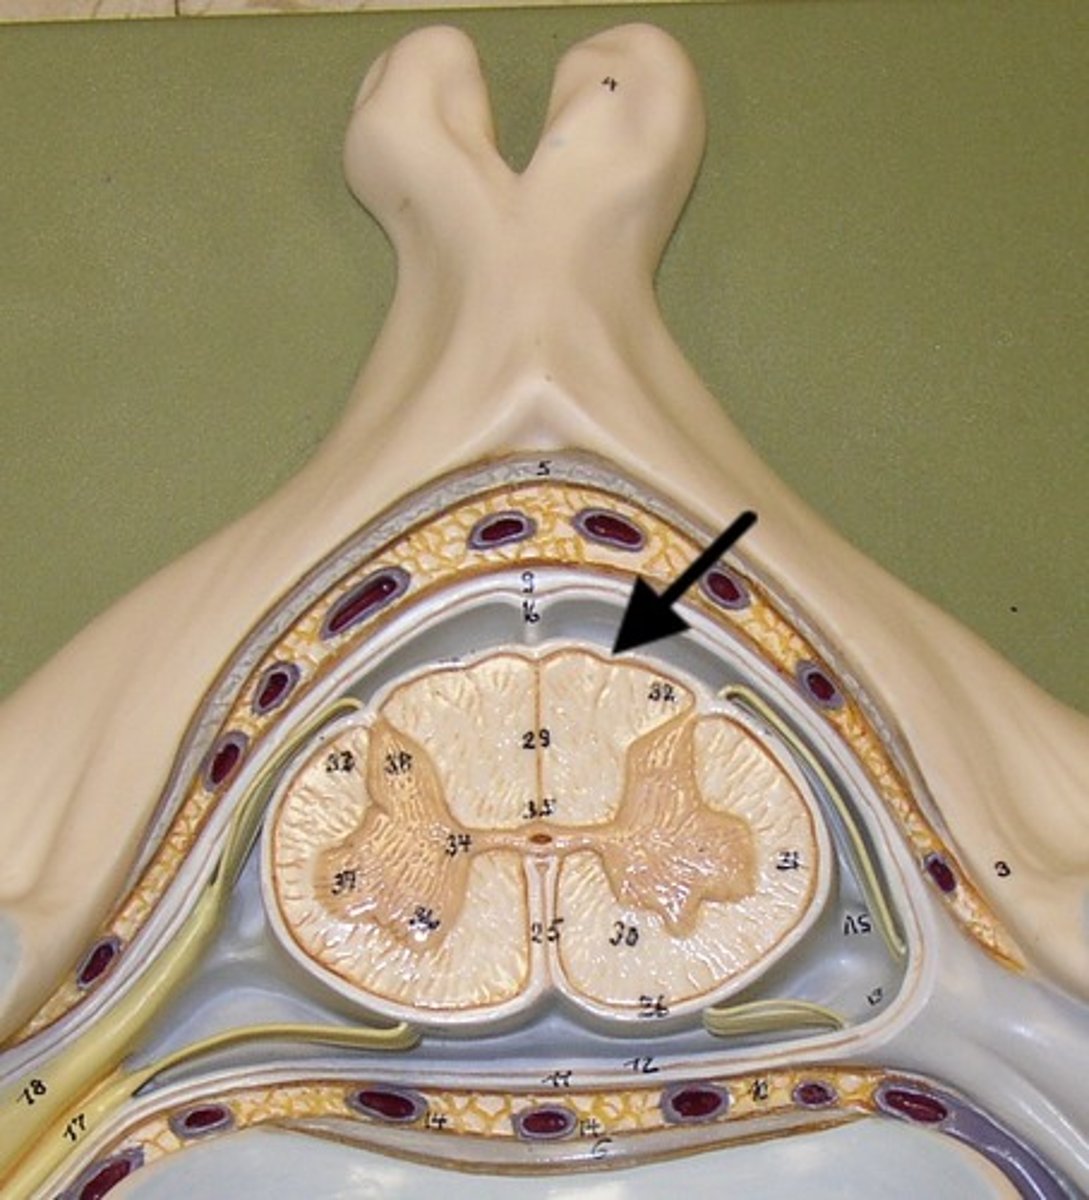

posterior median sulcus

anterior median fissure

posterior white column

anterior white column

lateral white column

posterior gray horn

anterior gray horn

lateral gray horn

gray commissure

central canal

epidural space

dura mater

subdural space

arachnoid mater

subarachnoid space

pia mater

denticulate ligaments